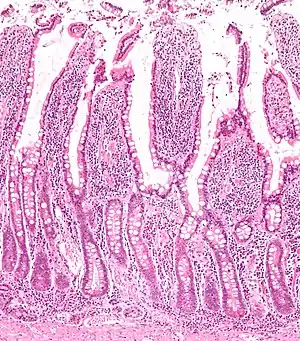

Microanatomy

The three sections of the small intestine look similar to each other at a microscopic level, but there are some important differences. The parts of the intestine are as follows:

| Layer | Duodenum | Jejunum | Ileum |

|---|---|---|---|

| Serosa | 1st part serosa, 2nd–4th adventitia | Normal | Normal |

| Muscularis externa | Longitudinal and circular layers, with Auerbach's (myenteric) plexus in between | Same as duodenum | Same as duodenum |

| Submucosa | Brunner's glands and Meissner's (submucosal) plexus | No BG | No BG |

| Mucosa: muscularis mucosae | Normal | Normal | Normal |

| Mucosa: lamina propria | No PP | No PP | Peyer's patches |

| Mucosa: intestinal epithelium | Simple columnar. Contains goblet cells, Paneth cells | Similar to duodenum | ? |

Digested food is now able to pass into the blood vessels in the wall of the intestine through either diffusion or active transport. The small intestine is the site where most of the nutrients from ingested food are absorbed. The inner wall, or mucosa, of the small intestine, is lined with simple columnar epithelial tissue. Structurally, the mucosa is covered in wrinkles or flaps called circular folds, which are considered permanent features in the mucosa. They are distinct from rugae which are considered non-permanent or temporary allowing for distention and contraction. From the circular folds project microscopic finger-like pieces of tissue called villi (Latin for "shaggy hair"). The individual epithelial cells also have finger-like projections known as microvilli. The functions of the circular folds, the villi, and the microvilli are to increase the amount of surface area available for the absorption of nutrients, and to limit the loss of said nutrients to intestinal fauna.

Each villus has a network of capillaries and fine lymphatic vessels called lacteals close to its surface. The epithelial cells of the villi transport nutrients from the lumen of the intestine into these capillaries (amino acids and carbohydrates) and lacteals (lipids). The absorbed substances are transported via the blood vessels to different organs of the body where they are used to build complex substances such as the proteins required by our body. The material that remains undigested and unabsorbed passes into the large intestine.